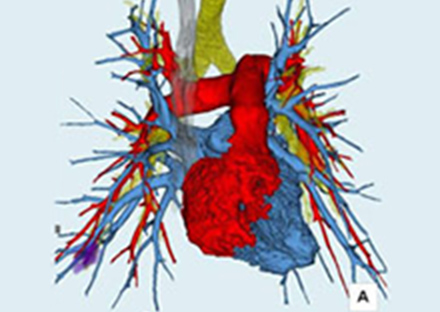

磁力と電波を使った検査でX線被ばく無しで任意の断面の撮影が可能です。脳や脊髄、臓器、腫瘍、関節、軟骨、軟部組織などの撮影に優れており、さらに血流を画像化することができるため、造影剤を使用せずに血管の状態を知ることができます。

dStreamテクノロジーによりフルデジタル化され良質な画像提供が可能です。

さらに開口径が70㎝のワイドボアと広くなり、患者さんに優しい設計になっています。